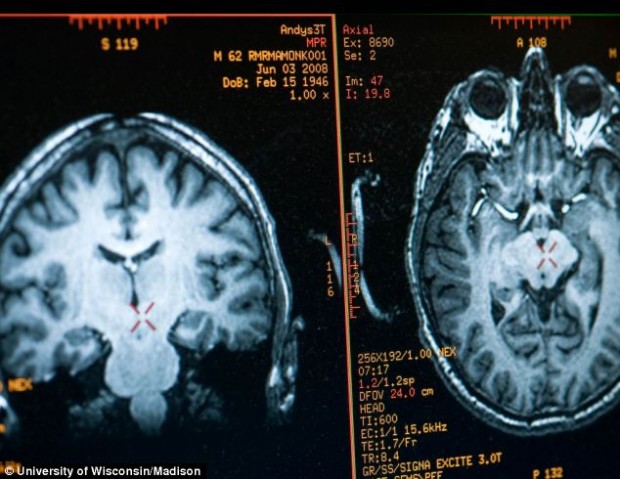

В рамках исследования, проводимого среди сотен людей, практикующих медитацию, невролог Ричард Дэвидсон из университете Висконсина, прикрепил к голове монаха 256 датчиков, которые должны были сканировать мозг Матье во время медитации.

Как показало сканирование, во время медитации Гамма волновая активность мозга Рикара существенно повышается.

Как полагают исследователи, чрезмерная активность в левой префронтальной коре мозга, по сравнению с правой, дает монаху аномально большой потенциал для счастья, а также понижает склонность в депрессиям.